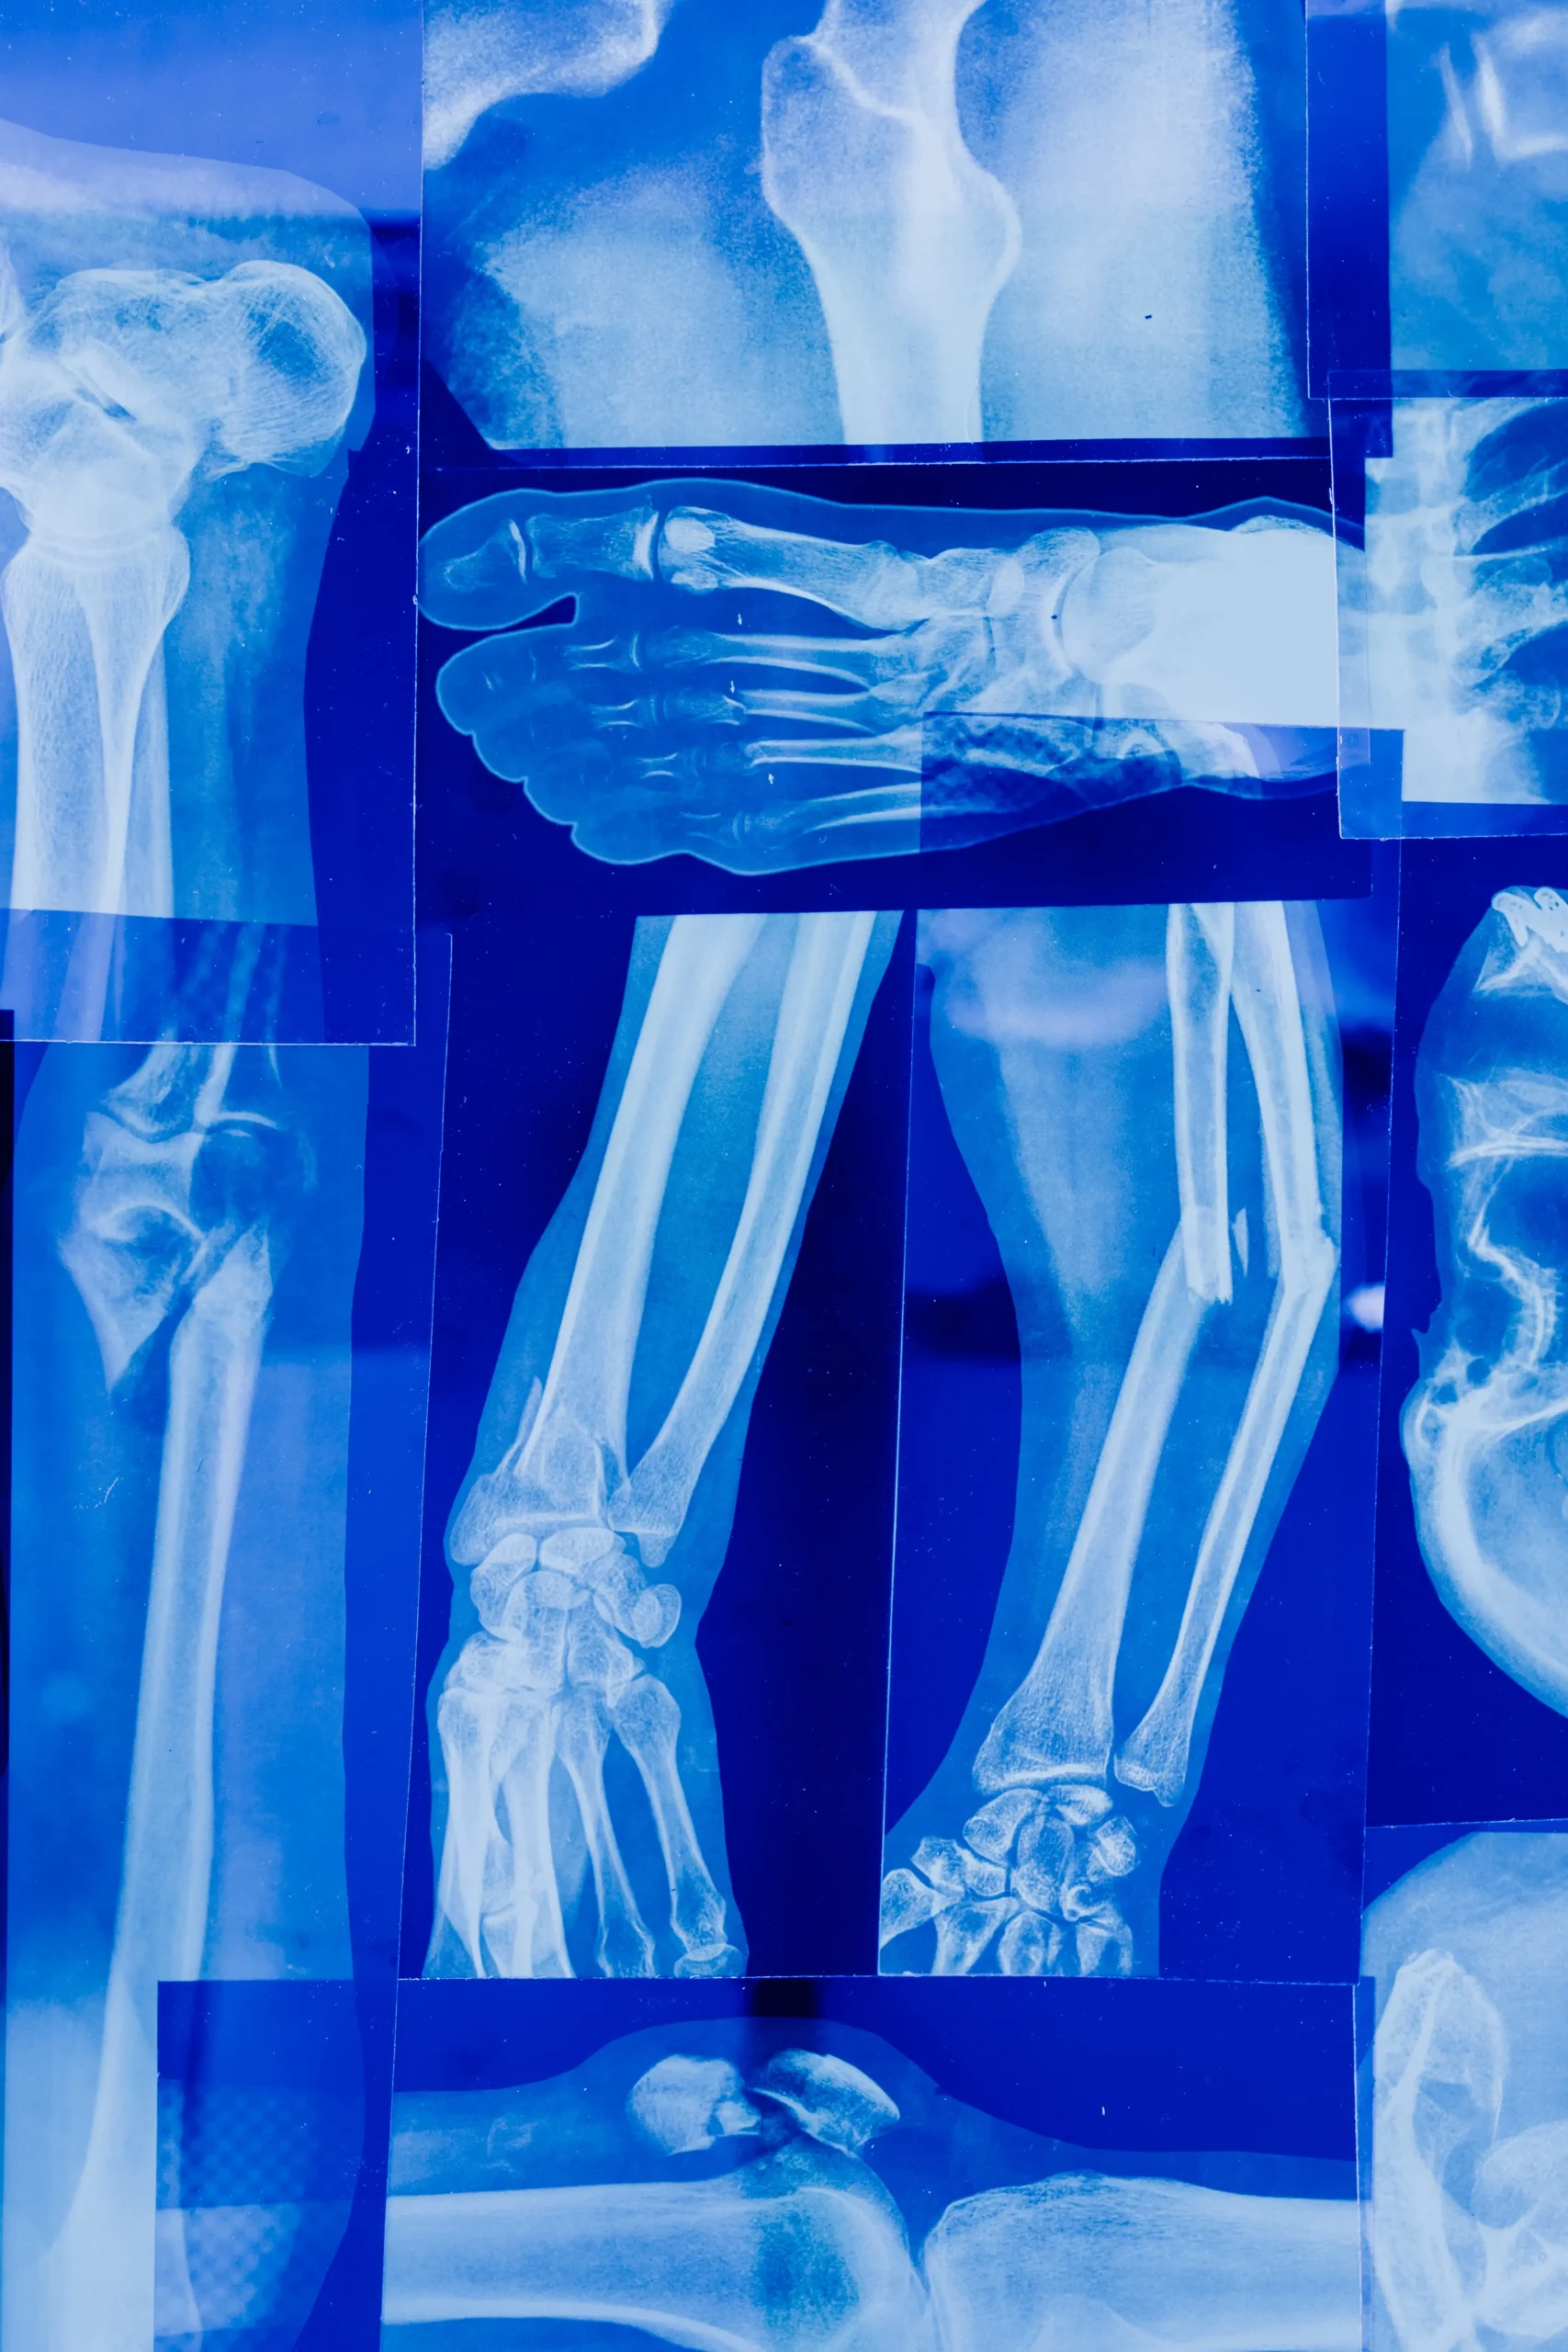

환자들은 보행 중 통증을 느낄 수 있으며, 앉았다가 일어나거나 계단을 오르내릴 때 더욱 심해질 수 있습니다. 이외에도 장시간 앉아 있는 경우 엉덩이와 다리의 변비감, 변형된 보폭, 그리고 다리의 긴장과 분비 등의 증상을 경험할 수 있습니다. 대퇴두 골두 무혈성 괴사증를 진단하기 위해서는 주로 X-ray 검사법이 사용되며, 때로는 MRI 스캔도 필요할 수 있습니다.

X-ray 검사는 대퇴골두 무혈성 괴사증을 정확하게 확인하기 위해 큰 도움을 줄 수 있는데, 환자의 뼈 구조와 관절의 변화를 시각적으로 확인할 수 있습니다. MRI 스캔은 보다 상세한 영상을 제공하여 진단에 도움을 줍니다. 진단이 이루어진 후,대퇴두 골두 무혈성 괴사증에 대한 치료 절차가 개시됩니다.